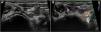

Due to the risks involved in surgical intervention and the scarcity of the evidence on endovascular treatment in newborns, currently limited to isolated case reports,1,2 the patient was managed conservatively with close clinical and radiological monitoring. Fifteen months later, the patient remains asymptomatic and has started to stand and walk without any problems associated with the pseudoaneurysm, which has exhibited progressive reduction in follow-up imaging (Fig. 3A and B). We present this case to demonstrate the feasibility of the conservative management of vascular complications in pediatric patients, an approach that requires very close clinical and radiological monitoring in experienced centers.